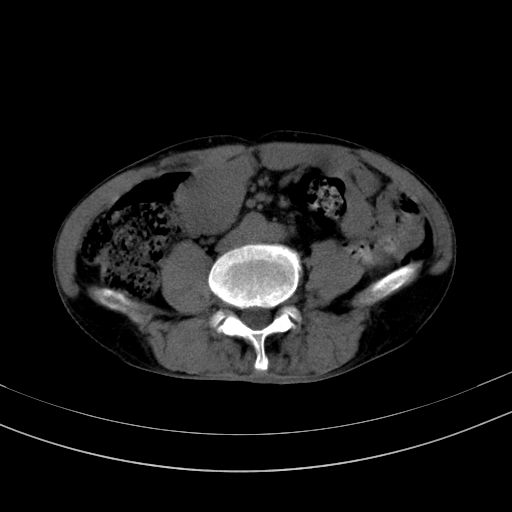

以下是引用37度在2010-1-9 14:37:00的发言:[br]1.双肾囊肿,左肾积水结石,.胆总管轻度扩张;[br]2.病灶在腹膜外,考虑纤维瘤。

以下是引用dyqct在2010-1-9 17:56:00的发言:[br]考虑:1.双肾囊肿,左肾积水结石、旋转不良。[br] 2.右侧腹直肌血肿或纤维瘤。[br]肠道准备不好。做个增强。